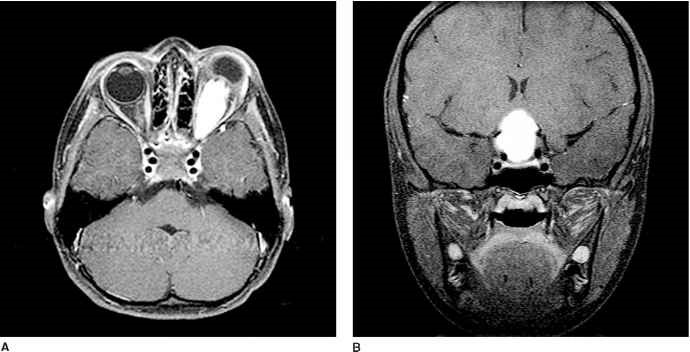

MRI:表现为T1WI中等偏低信号,T2WI明显高信号。肿瘤累及视神经管内段时,多引起眶内段蛛网膜下腔脑脊液循环受阻,引起蛛网膜下腔明显增宽,显示为病变周围长T1长T2信号,与脑脊液信号一致。增强后肿瘤呈较明显强化。